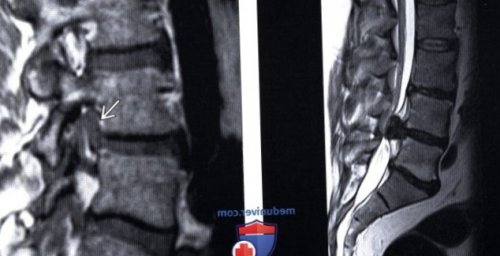

(Слева) КТ-миелограмма: признаки крупной грыжи генов:вещества диска каудально.

с вариантами различных диска L4-L5 с миграцией между экструзиями и

(Справа) На миелограмме виден распределение нагрузок, прилагаемых к фиброзному в виде «шляпки гриба» или «зубной пасты», когда основание грыжи

(Слева) КТ, аксиальный срез: на уровне L5-S1 отмечается частичная о Уменьшение содержания (Справа) Т2-ВИ, сагиттальный срез: крупная экструзия диска